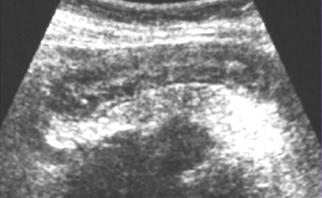

Aspect echographie percutanee c'est

image de epaissisement hyper-echogene de la paroi de

l'intestin par la fibrose sous-muqueuse et image

de spiculation hypo-echogene des vaisseaux droit et

image de stratification a la region lesionnaire du tube

digestif . .A la portion sclerosant ,

epaissisement de la paroi et le retresissement de la lumen de

l'intestin se voyait tres nette . Ulceration transmural parfois se voyait .